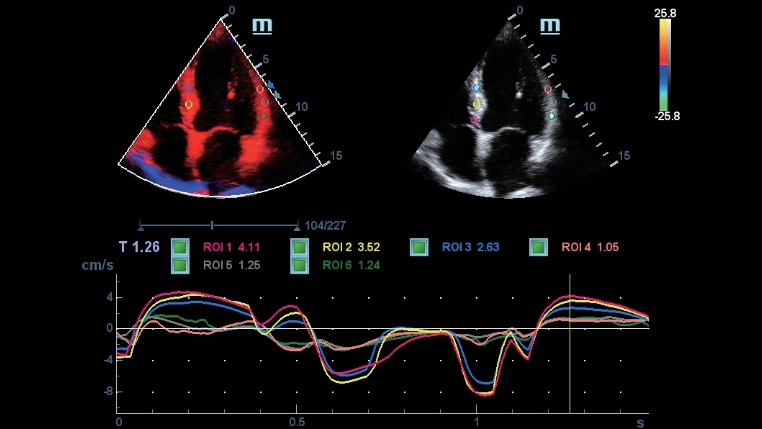

TecnologĂas de obtenciĂłn de imĂĄgenes clĂĄsicas: mejora de la calidad para el diagnĂłstico

Mediante la aplicaciĂłn de tecnologĂas de obtenciĂłn de imĂĄgenes clĂĄsicas, que se migran de sistemas de diagnĂłstico por ultrasonido consolidados, el DC-40 con Full HD le proporciona una mejor calidad de imagen con el grado de detalle que necesita.

Gama completa de herramientas de aplicaciĂłn: garantĂa de precisiĂłn y comodidad

iTouch

El DC-40 con Full HD incorpora una gama completa de herramientas que maximizan la precisiĂłn en el diagnĂłstico con eficiencia y comodidad. La cobertura general de imĂĄgenes, obstetricia, ginecologĂa y cardiologĂa del DC-40 con Full HD le proporciona una soluciĂłn completa para aplicaciones clĂnicas generales, con un flujo de trabajo simplificado para actuar con eficiencia.